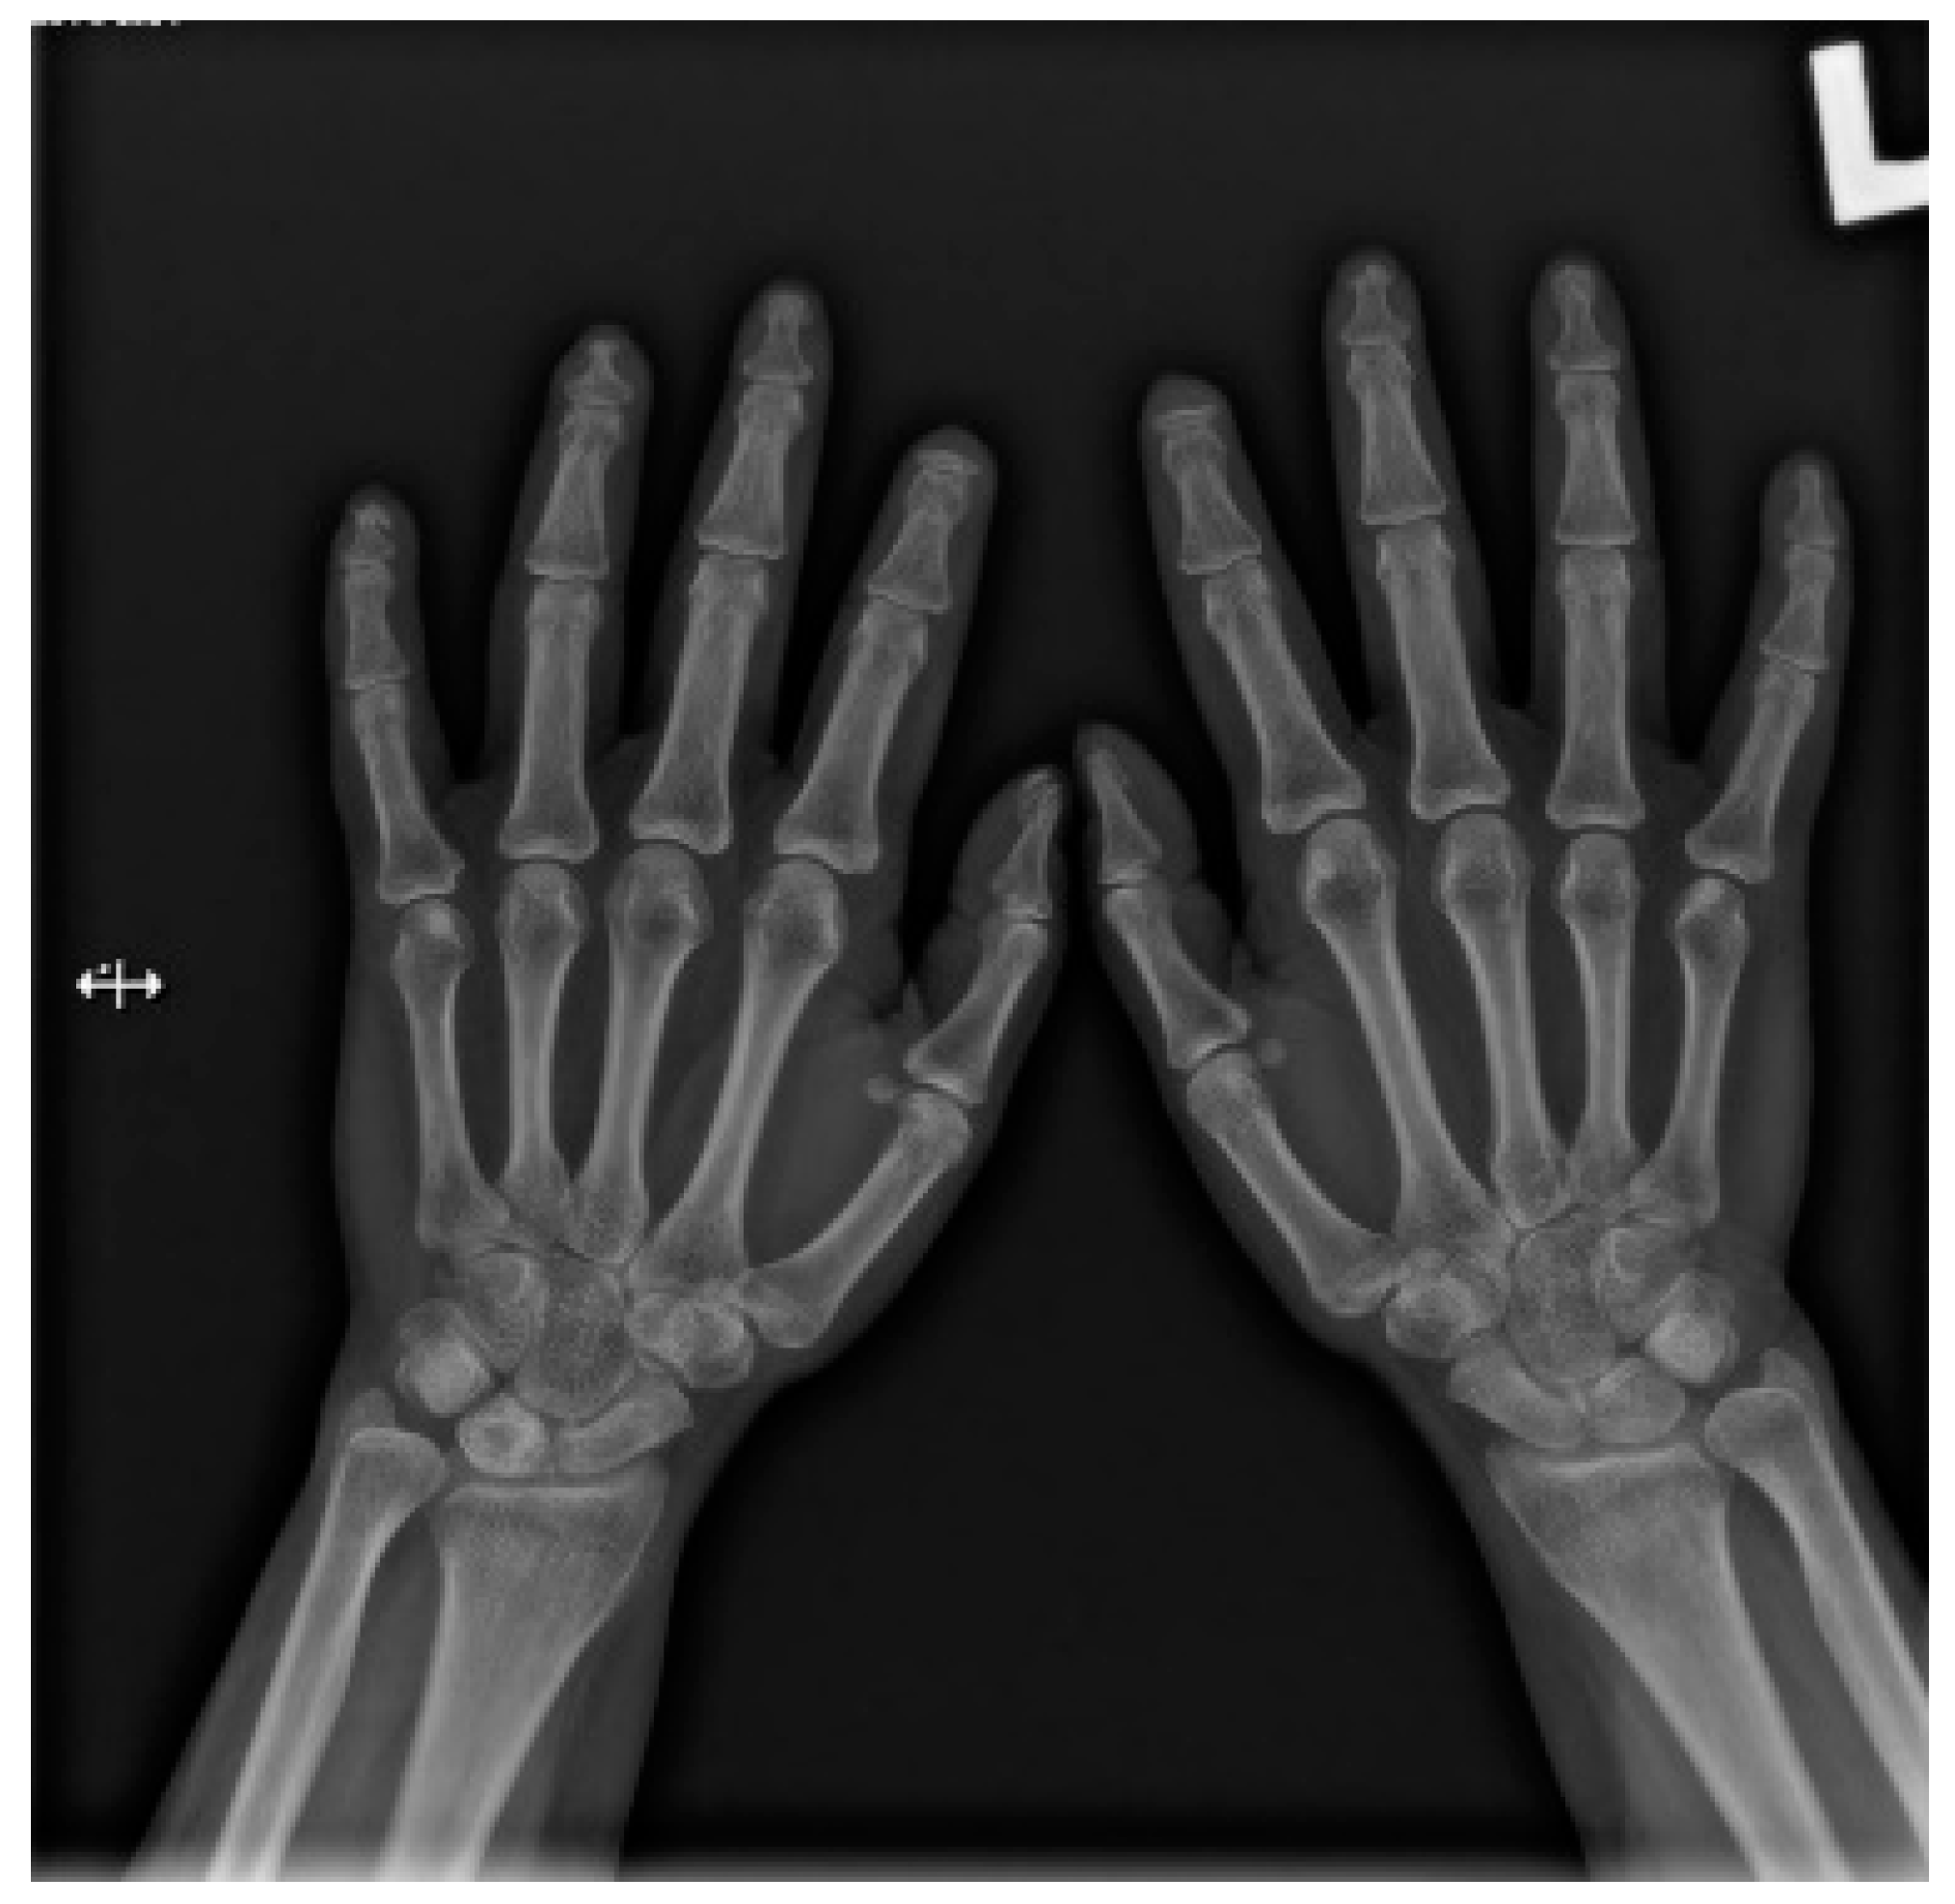

Hands are the most characteristic location of lesions in SSc. Articular symptoms are seen in 10–60% of patients at the time of diagnosis. Features allowing to distinguish changes caused by scleroderma from symptoms of other diseases are predominantly acro-osteolysis, calcifications, and soft-tissue thinning, which are all visible on radiographs [13]. According to the latest research, acro-osteolysis (Figure 1 and Figure 2) is seen in about 16% of patients [14]. The distinctive ‘sharpened pencil’ sign is caused by resorption of the terminal tuft of distal phalanges; this symptom is usually more pronounced on the palmar surface of phalanges. A correlation between acro-osteolysis and digital ulcerations was observed. The less common locations where bone resorption might be seen in SSc patients include medial parts of the ribs, distal end of the radial and ulnar bones, clavicle, and mandibulum [15,16]. Although acro-osteolysis is a common finding in SSc, a number of other pathological entities might be also associated with this symptom—including rheumatological disorders, psoriatic arthritis, hyperparathyroidism, and thermal injuries [17,18].

Figure 1.

A-P view of the hand radiograph in a patient with systemic sclerosis shows acro-osteolysis especially expressed in the distal phalanx of the second finger of the left hand and in the distal phalanx of the second finger of the right hand.